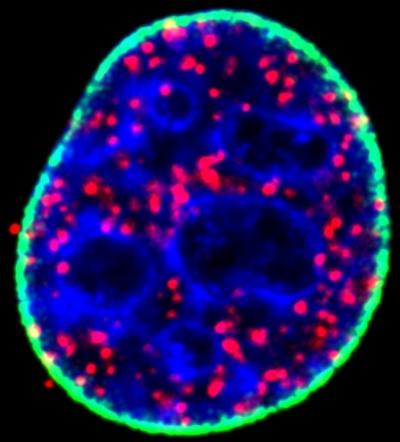

Typically, explains Anderson of the UW School of Medicine and Public Health, the p53 protein serves as "the guardian of the genome," initiating the repair of DNA damaged by ultraviolet radiation, chemicals or other means and preventing tumor growth. When mutated, however, the protein goes rogue, becoming more stable and abundant than its unmutated counterpart, accumulating in the nucleus of the cell and causing cancer.

The research team, which includes study lead authors and postdoctoral fellows Suyong Choi and Mo Chen, found a new mechanism that drives this stability. The culprit: an enzyme called PIPK1-alpha and its lipid messenger, known as PIP2, which seem to behave as master regulators of p53.

The Wisconsin team showed that when a cell is stressed, whether by DNA damage or other means, the enzyme associates with p53 and produces PIP2, which binds strongly to it and promotes interaction between p53 and molecules known as small heat shock proteins. This stabilizes the protein complex, setting the stage for cancer, including aggressive cancers such as triple negative breast cancer.

The findings, Anderson adds, were a little puzzling because the catalytic enzyme and PIP2 are typically and most abundantly found in cell membranes and not in the cell nucleus interior, where mutant p53 does its damage.

"This lipid pathway is weird," he says. "Lipids are supposed to be in membranes and this is not in a membrane compartment."